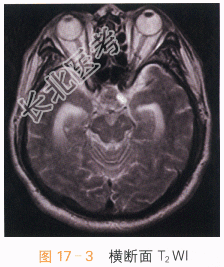

男,56岁,头痛1年余,进行性加重2月。

读片分析:头颅CT平扫见鞍上异常软组织影,并可见多发钙化,局部见“蛋壳样钙化”,横断面T₁W见鞍上异常软组织信号灶,呈等高信号影,T₂WI见病灶表现为囊实性肿块;增强扫描实性部分可见明显强化,囊性部分未见明显强化,但正常垂体结构能显示。结合患者临床,可考虑颅咽管瘤。